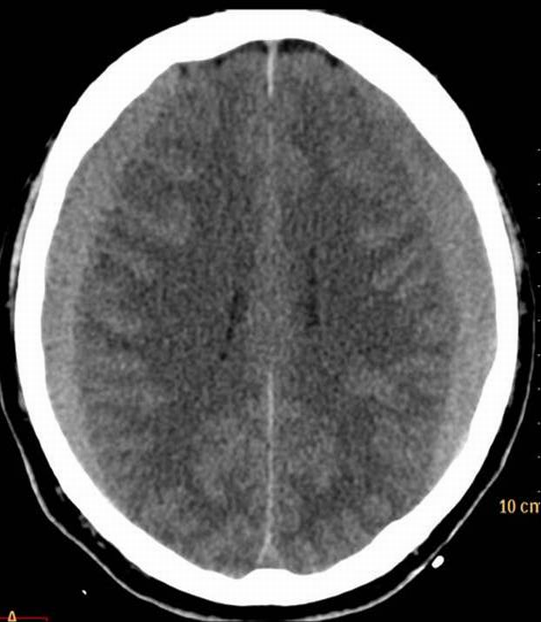

The key question whether the patient ha intracranial hematoma, which causes mass effect and later leads to vasoconstriction. In the presence of open skull fracture signed by liquorrhea severe infection and herniation might occur. To exclude intracranial hemorrhage CT is the modality of choice.

All three types of intracranial hematoma can occur as a result of head trauma:

• Selection of adequate imaging modality should be based on whether an intracranial or extracranial localization is suspected. Intracranial diseases are discussed in the neurology chapter. In emergency cases CT (both unenhanced and contrast enhanced) is the primary imaging modality, occasionally MRI is also used to evaluate lesions of the brain.

• In the stoke focal neurological signs might be helpful to establish a diagnosis while headache is less frequently seen. The diagnostic work-up of ischemic stroke is described in more detail in the neurology chapter. Headache, sudden non ceasing pain may indicate hemorrhagic stroke (e.g. subarachnoideal bleeding, SAH). An unenchanced CT can be diagnostic, it is widely available and fast, even compared to the most advanced MRI sequences. In SAH to guide the therapy site of bleeding has to identified therefore an MR or CT angiography is usually included in the work-up protocol.